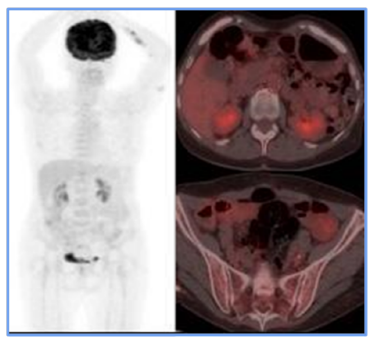

As a result, the treating hematologist recommended a second-line chemotherapy regimen (RICE) for 3 cycles. At the end of these sessions, a follow-up PET scan revealed the resolution of adenopathy in the obturator chain (Figure 3), demonstrating a complete metabolic response. Based on these findings, the patient was declared in remission. Given the favorable evolution, maintenance immunotherapy was initiated with a standard-dose Rituximab regimen for low-grade lymphoma, administered every 2 months for 2 years. As for the writing of this report, the patient has successfully completed 9 cycles and remains in remission.

Figure 3

PET CT scan following the rescue scheme. It presents the resolution of adenopathy in the proper internal iliac chain, which is related to morphological and metabolic responses to medical treatment.

For staging, PET-CT (F18-FDG) is a crucial tool. Initially, it allowed for documentation of both nodal and extranodal involvement, establishing tumor viability and aiding in follow-up and evaluation of treatment response. The Deauville 5-point visual scale [7] was used to assess treatment response. In this case, the PET-CT documented persistent disease (Deauville 4), which influenced treatment decisions and led to escalation of the medical management. A subsequent PET-CT (F18-FDG) performed after rescue therapy demonstrated a complete metabolic response at the end of treatment [8].

In the case presented here, the patient showed a favorable response to chemotherapy, achieving complete remission and surviving for two years to date. Lymph node and extranodal involvement, along with immunohistochemical findings, enabled the diagnosis and timely treatment initiation (Figure 1). The partial metabolic response observed in the post-treatment PET (Figure 2) led to the decision to escalate the treatment to second-line RICE chemotherapy. Eventually, a new PET-CT (F18-FDG) post-treatment (Figure 3) confirmed a complete metabolic response.